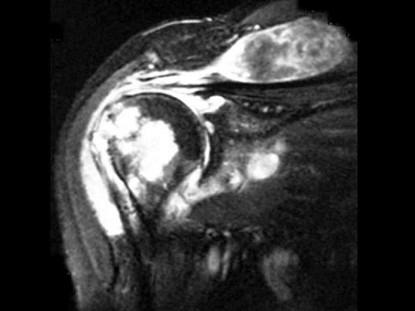

问题 女,71岁,左肩痛,系统性红斑狼疮服用高剂量的类固醇半年,结合图像,最可能的诊断是?(?)

选项 A.化脓性关节炎 B.类风湿关节炎 C.骨纤维肉瘤 D.肱骨头缺血坏死 E.肩关节结核

答案 E